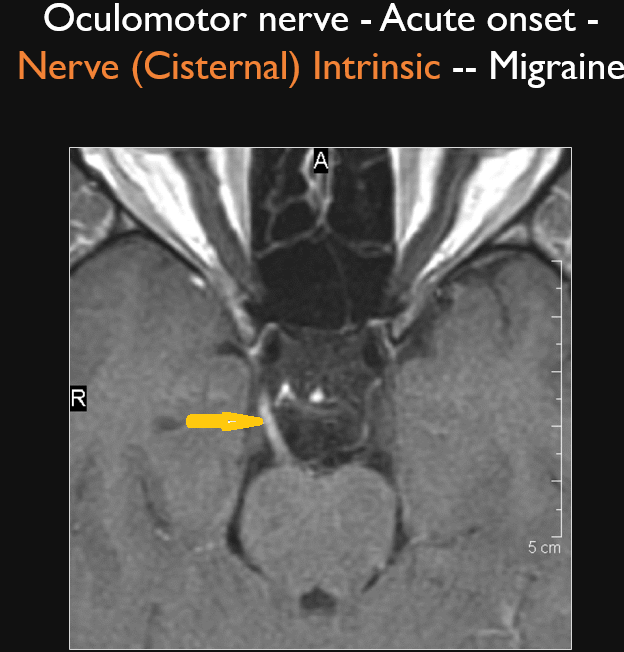

There is abnormal enhancement and/or enlargement of the cisternal segment of the third, fourth and/or sixth cranial nerve. [Yes/No]

There is a structural abnormality along the cisternal segment of the third, fourth and/or sixth cranial nerve. [Yes/No]